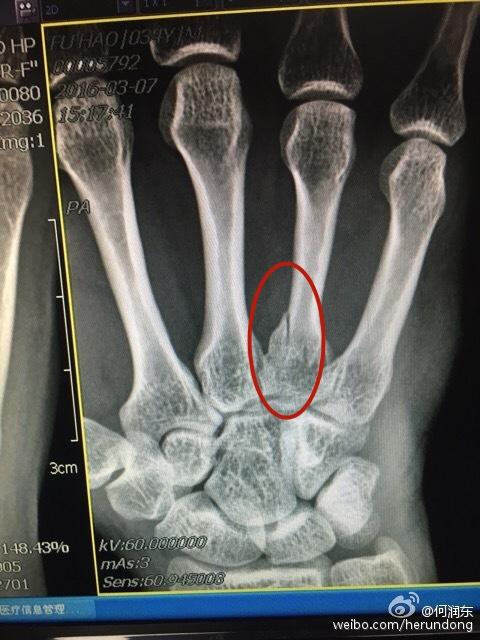

无论怎么看何润东这次的受伤都要比2016年严重得多,那次也是右手,X光片显示无名指有个地方的骨头裂开了,裹了厚厚的石膏,三个星期的时间基本就好完了。